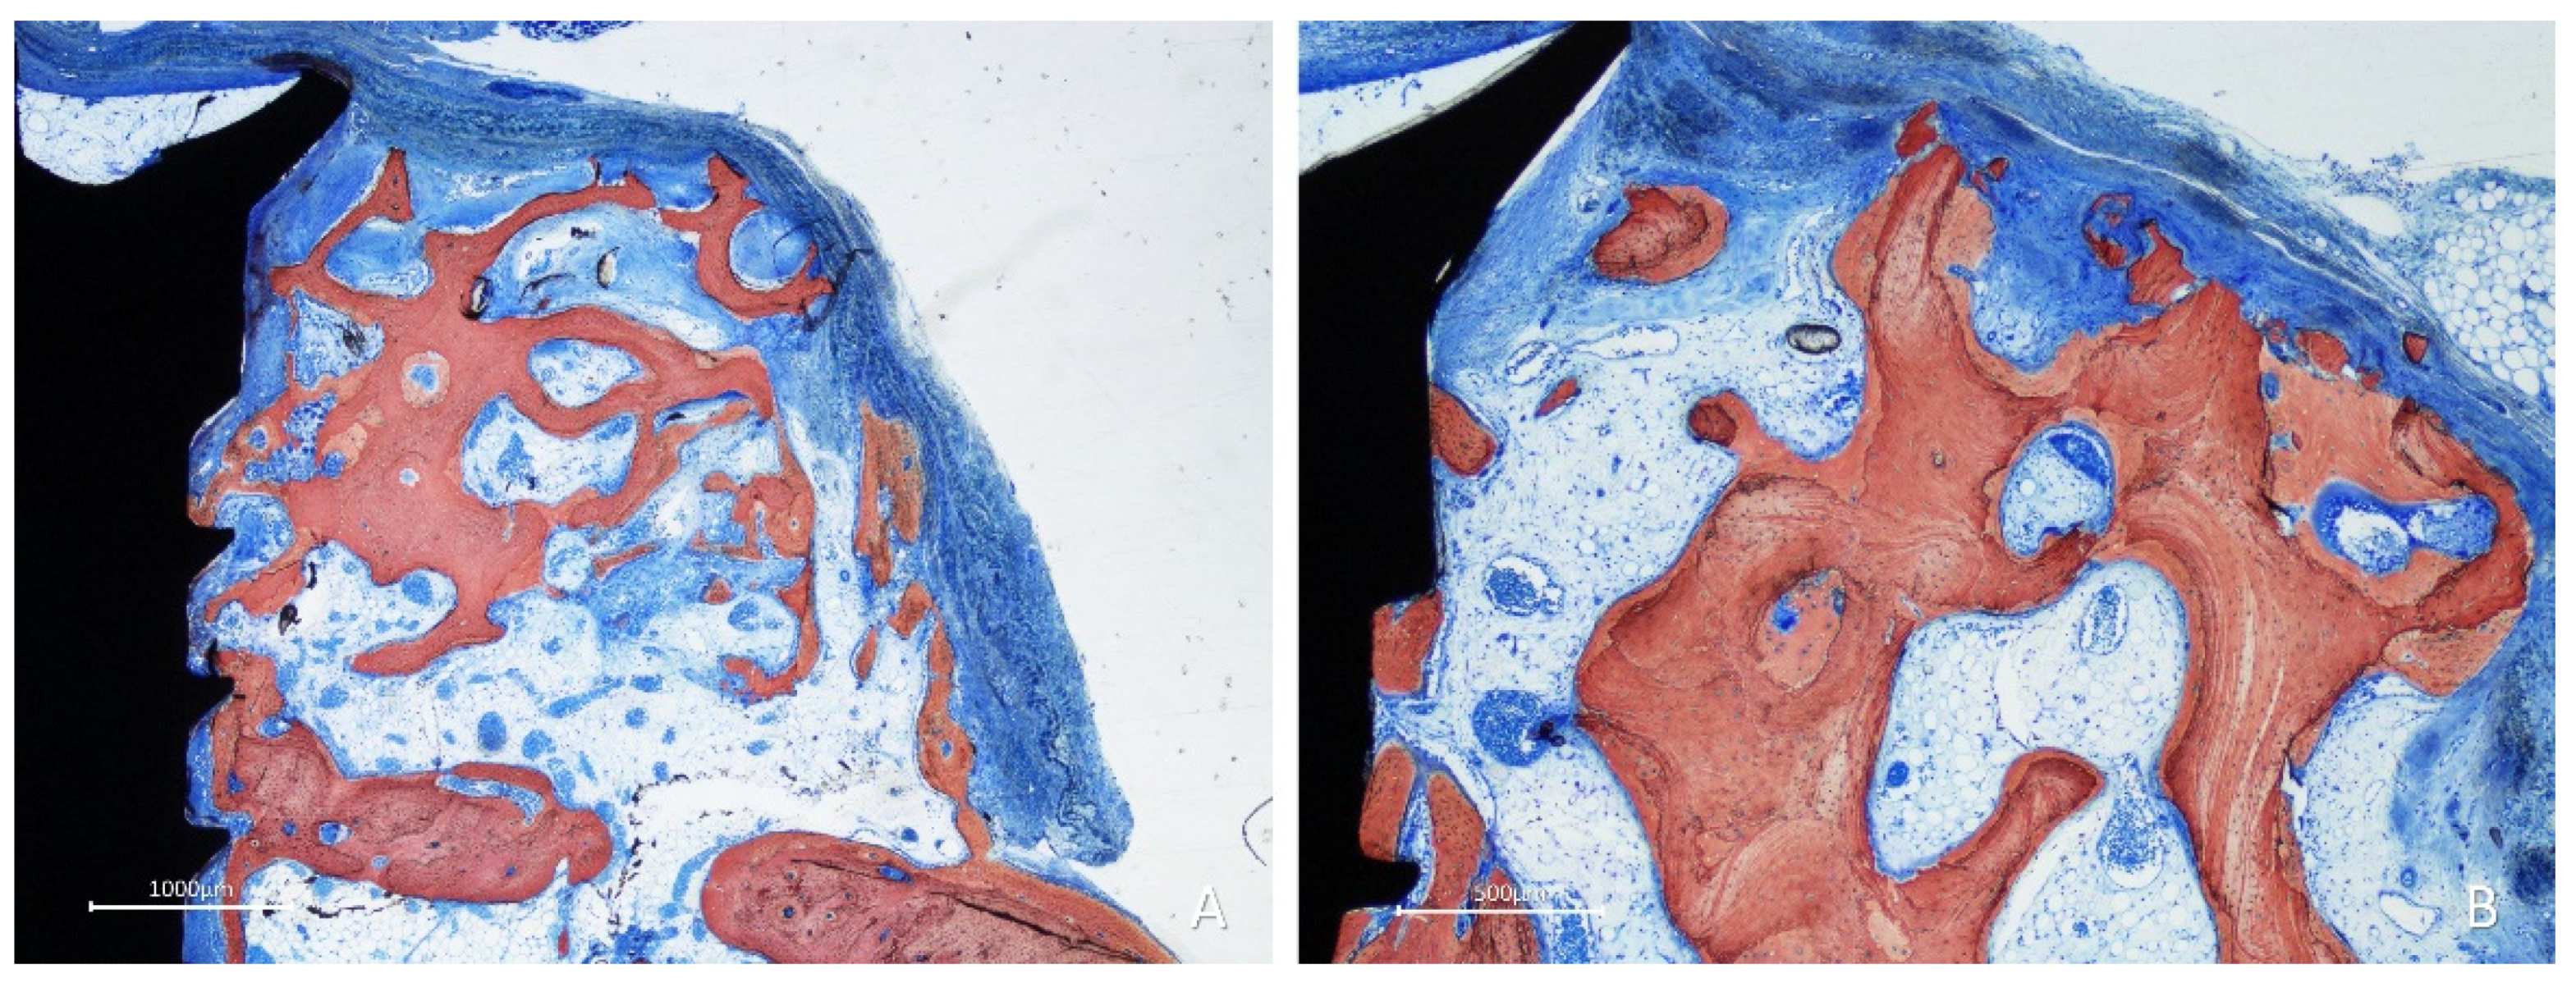

After 10 weeks of healing, bone was found lining the surface of the graft in the onlay group (Figure 7A,B), while the space included among the trabeculae was filled with bone marrow and provisional matrix.

Figure 7. Photomicrographs of ground sections showing healing aspects at onlay graft sites after 10 weeks. A, the space included among the trabeculae was filled with bone marrow and provisional matrix. B, note new bone deposed onto the trabeculae. Stevenel’s blue and alizarin red stain.